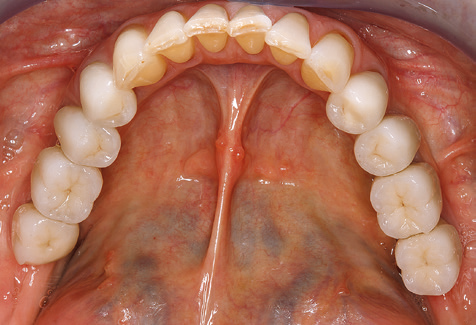

A 52-year-old patient presented in our clinic for the first time in 2004 following tooth loss in the third quadrant, expressing a desire for a new prosthetic restoration. Periodontal and radiological diagnostics revealed the need for extensive periodontological treatment. In addition, teeth 48, 28 and 27 were attributed a very poor prognosis and were subsequently extracted (Fig. 1). Following the successfully completed, systematic periodontological treatment, a fixed dental implant was inserted with the introduction of five implants in tooth regions 35, 36, 37, 46 and 47. Prosthetic treatment of the natural teeth was effected with veneered zirconium dioxide ceramic crowns; the implants were composed of two-piece, individual zirconium dioxide abutments and similarly veneered crowns made of a zirconium dioxide ceramic (Cercon base colored, Dentsply Sirona Lab). Definitive insertion of the prosthetic restoration occurred in 2005.

Due to the presence of periodontal disease, SPT was performed every three months in the first years following the insertion. The patient demonstrated a high degree of motivation and good compliance. The pocket depths recorded annually revealed a stable periodontal situation with a BOP index of below five per cent. On the basis of the stable periodontal situation and good cooperation on the patient’s part, the recall interval was extended to every six months as of the sixth year of the prosthetic function phase. Following the change in the recall interval, the respective annual documentation of the periodontal status continued to reveal a stable periodontal situation with no increase in the pocket depths and a BOP index below five per cent (Fig. 2a and b).

The patient continues to visit the clinic every six months for SIT. In the following, the patient is taken as an example for demonstrating the individual working steps in a structured SPT session as it has been performed with barely any modifications over the last 12 years. Of course, some new materials and devices have been integrated into the concept over the years. This clinical case report presents the current material and device concept.